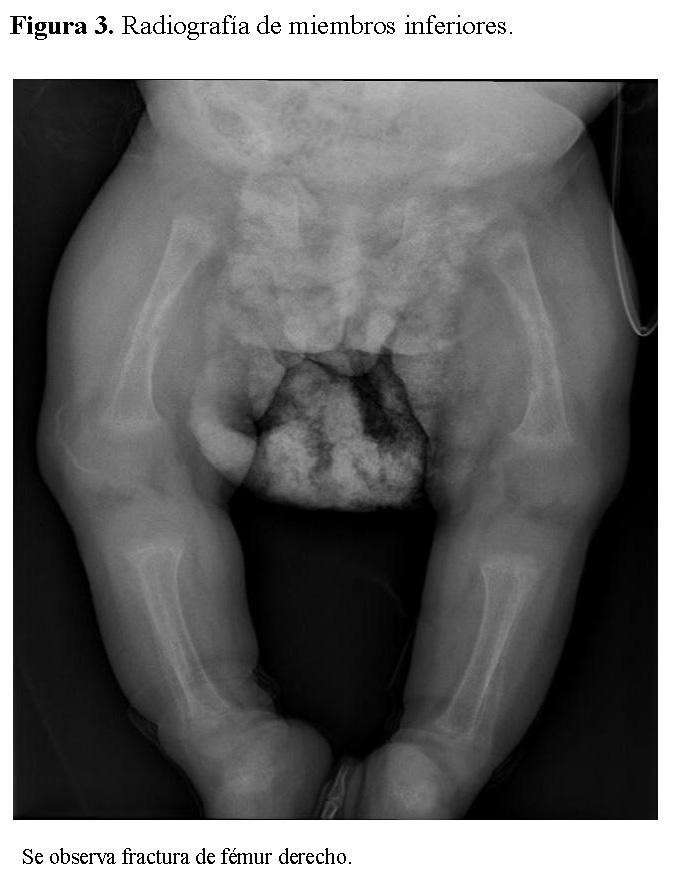

Chest radiography showed bilateral heterogeneous parenchymal infiltrates, pleural thickening, and right-sided rib fractures in the consolidation phase (Figure 1). Radiographs of long bones revealed severe osteopenia, periosteal reaction, and multiple pathological fractures, including the right and left humerus, right ulna, and right femur (Figures 2 and 3).

Figure 3.